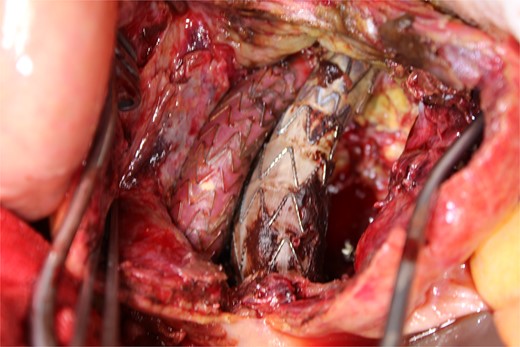

This time, he was brought to the emergency department with a chief complaint of abdominal pain. His medical history includes Stage 4–5 chronic kidney disease (CKD), with an estimated glomerular filtration rate (eGFR) of approximately 15 mL/min/1.73 m2, secondary to nephrosclerosis and diabetic nephropathy, as well as persistent atrial fibrillation, which was treated with warfarin. Upon admission, laboratory results revealed a hemoglobin level of 6.2 g/dl and a prothrombin time—international normalized ratio (PT-INR) of 6.05. Contrast-enhanced CT demonstrated an AAA measuring 118 × 107 mm, enlarged from 98 × 94 mm 2 months prior, and left retroperitoneal hematoma. IMA and one pair of lumbar arteries were enhanced only in the delayed phase, but blood flow into the aneurysm was not clearly observed (Fig. 1). Given that the landing zones and overlaps of the stent grafts were satisfactory (Fig. 2) and that no type I or type III endoleaks were identified, a ruptured AAA due to TIIEL from the lumbar artery or IMA was highly suspected. We administered 3000 IU/kg of lyophilized human prothrombin complex concentrate in response to the significant prolongation of PT-INR and proceeded with open surgery for ligation of the feeding artery and aneurysmorrhaphy. Intraoperatively, no pulsation was found on the aneurysm. Incision of the aneurysm revealed a large amount of thrombus, which was removed, and then pulsatile bleeding was identified from a lumbar artery (Fig. 3), the ostium of which was sutured from within the aneurysm. This was consistent with the left lumbar artery of the pair enhanced on the preoperative CT and was suspected to be responsible for the rupture. Oozing was also noted from several other lumbar arteries, which were similarly sutured closed. No leak was observed from the proximal or distal ends, nor from the junctions of the stent grafts, and no damage to the stent grafts was observed (Fig. 4). Following this, aneurysmorrhaphy was performed, and the abdomen was closed. The postoperative course was uneventful. A plain CT on postoperative day (POD) 14 showed a reduction in the aneurysm size with no apparent leaks (Fig. 5). The patient was discharged home on POD 24. Although the preoperative eGFR was 8.8 ml/min/1.73 m2, no postoperative deterioration was observed. It gradually improved back to baseline, and dialysis was not required during the follow-up period.

A photo taken from the caudal side of the patient. No endoleaks other than the type II endoleak were observed.